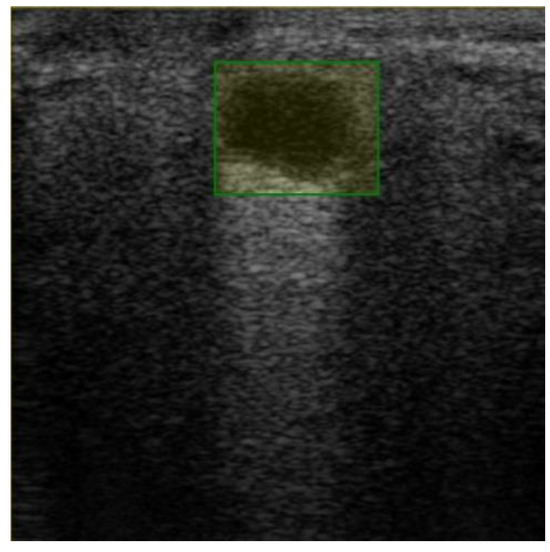

Since our goal was to determine the overlap ratio between the predictions and the labels made by the experts in the field, we searched for alternative ways of reaching our objective, so we applied another metric, IoU. The formula used to calculate IoU is presented in Equation (4) [23]. The better the alignment between the predictions and the label, the more accurate the network. Since this technique verifies each label individually, we averaged the results into a boxplot (Figure 9). The overlap ratio between the predictions and labels ranged between 47% and 84% on the test images, with an average of 74%. Few aberrant labels were ignored. One of the final predictions can be seen in Figure 10.

Figure 10. Predictions with an IoU overlap of 81%.